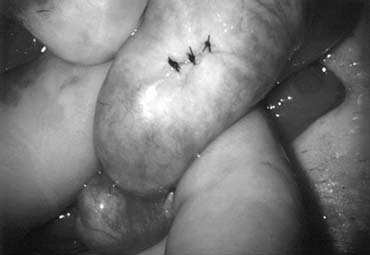

Bilateral 1-cm transverse scrotal incisions provide good exposure with a minimum of scrotal skin bleeding (Fig. 1). Alternatively, a single vertical incision in the median raphe may be employed. Use of loupes or an operating microscope allows ready identification of a relatively avascular area on the tunica albuginia where an incision may be made. A 3- to 4-mm incision is made in the tunica albuginea with a 15-degree microknife (Fig. 2). A pea-size sample of seminiferous tubules is excised with razor-sharp iris scissors (Fig. 3). When handling testis biopsy material for permanent fixation, it is important to avoid tissue traumatization by forcep handling in any way as this may distort the testicular architecture.

Fig. 1. A .5-cm transverse incision over upper lateral or medial aspect of testis. Hemostats hold open edges of tunica vaginalis.